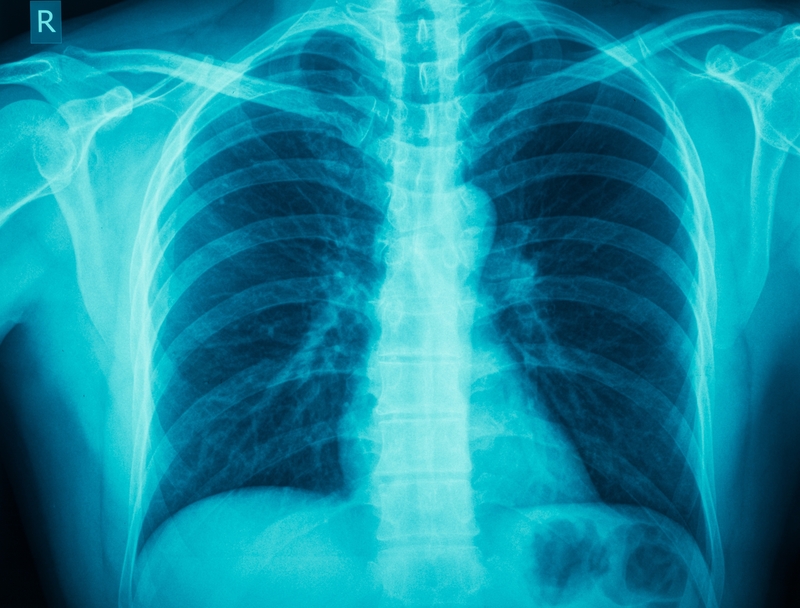

台灣胸腔暨重症加護醫學會公共事務組北區委員柯信國表示,據統計,台灣一年有超過5,000人因肺阻塞(COPD)死亡,雖特殊時期民眾對到大醫院就醫較抗拒,不過,很多肺部問題要透過肺功能檢測、照X光才能更精準診斷,因此建議民眾,若「咳、痰、喘」三大症狀持續3週以上,應至胸腔內科檢測,也盼此活動能成為高風險族群及早診斷的契機。